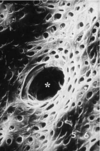

Changes in the dental papilla associated with initiation of dentin formation. An acellular zone (*) separates the undifferentiated cells of the dental papilla (preodontoblasts, pOd) from the differentiating inner enamel epithelium (ameloblasts, Am).

Preodontoblasts develop into tall and polarized odontoblasts (Od) with the nucleus away from the matrix they deposit at the interface with ameloblasts. The matrix first accumulates as an unmineralized layer, predentin (PD), which gradually mineralizes to form mantle dentin (D). Odp, odontoblast process; SI, stratum intermedium; SR, stellate reticulum.